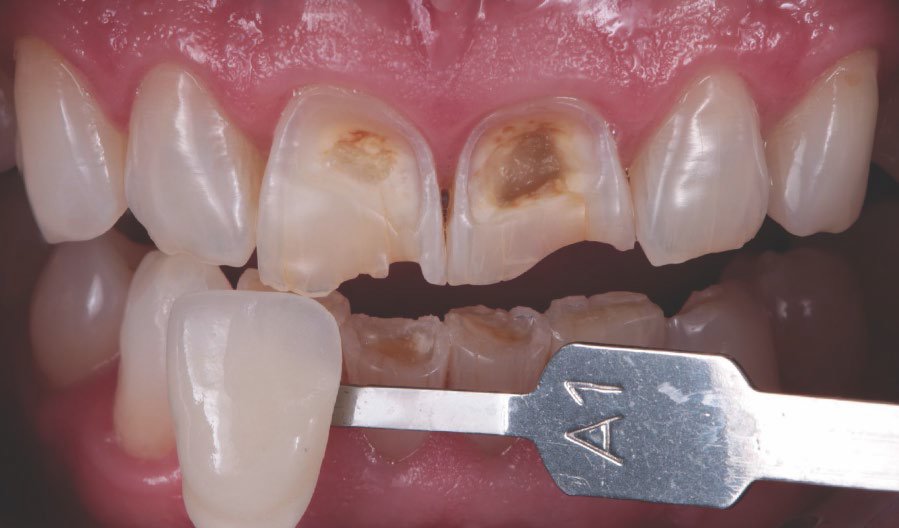

Preoperative frontal view of the patient’s teeth, showing severe erosive tooth wear on the vestibular surfaces and incisal edges.

Tooth shade was determined with the aid of the VITA classical A1-D4® shade guide. The shade A1 matched the sound tooth structure. This corresponded with 3M™ Filtek™ Universal Restorative shade A1.

Tooth shade was determined with the aid of the VITA classical A1-D4® shade guide